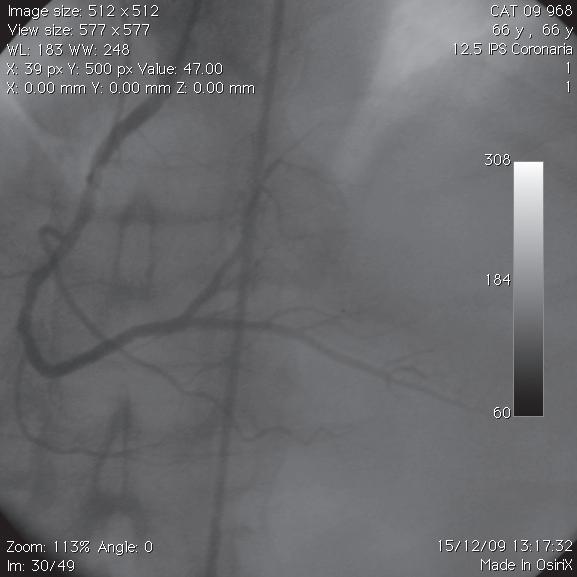

Nesta figura, observa-se a evolução da prova de esforço de um doente com uma coronariopatia grave. Prova de esforço (protocolo de Bruce).

A. O ECG feito em repouso e imediatamente antes da prova de esforço mostra um ritmo sinusal com frequência de 90/min e sem alterações dignas de nota.

B a I. Verifica-se que ao 3.º minuto de esforço nada há a salientar. A partir do 6.º min de prova, observa-se um supradesnivelamento do ponto J e do segmento ST de 3 mm em DII, DIII e aVF (mostrando uma lesão obstrutiva grave da artéria descendente posterior) e de V1 a V4 (por lesão obstrutiva grave da coronária descendente anterior) que se mantêm na recuperação, no pós-esforço imediato e no 1.º min da recuperação, e aos quais se agrega a imagem em espelho de ST-T em aVL. No 3.º min de recuperação e a partir do 2.º complexo há uma paragem sinusal de 3,2 seg (não há registo de complexos em aVR, aVL e aVF), ao que se segue um ritmo de escape hissiano com frequência de 37/min, retomando o ritmo sinusal normal apenas ao 5.º min de recuperação. Por este comportamento pode dizer-se que muito provavelmente há uma obstrução grave da coronária direita proximal (que dará posteriormente a artéria descendente posterior, como já foi dito) e antes da emergência da artéria sinusal, além de uma obstrução grave da artéria descendente anterior. A coronariografia mostrou uma lesão ostial de 90% da coronaria direita e uma lesão proximal de 90% da descendente anterior.

figura 24.4 – Positividade de prova de esforço por supradesnivelamento do ponto J e do segmento ST.

prova dE Esforço positiva E localização da obstrução coronária Numa prova de esforço positiva, o infradesnivelamento de ST, numa ou mais derivações, não nos permite afirmar em que coronária se encontra a lesão. No entanto, se essa positividade for dada por supradesnivelamento de ST, podemos afirmar com segurança que a lesão obstrutiva corresponde à coronária que vasculariza essa parede, como já foi referido no Capítulo 18. Por exemplo, o supradesnivelamento de ST em DII, DIII e aVF corresponde a uma lesão grave da descendente posterior, se, concomitantemente, se observarem arritmias supraventriculares, arritmias ou paragens sinusais, fibrilhações auriculares, etc. Pode, então, concluir se que a obstrução se situa na coronária direita proximal, antes da saída da artéria do nódulo sinusal (Figura 24.4). Se um supradesnivelamento de ST se observa de V1 a V3 ou V4, tal corresponde a uma lesão grave da artéria coronária descendente anterior (Figura 24.4). incompEtência (ou insuficiência) cronotrópica sinusal